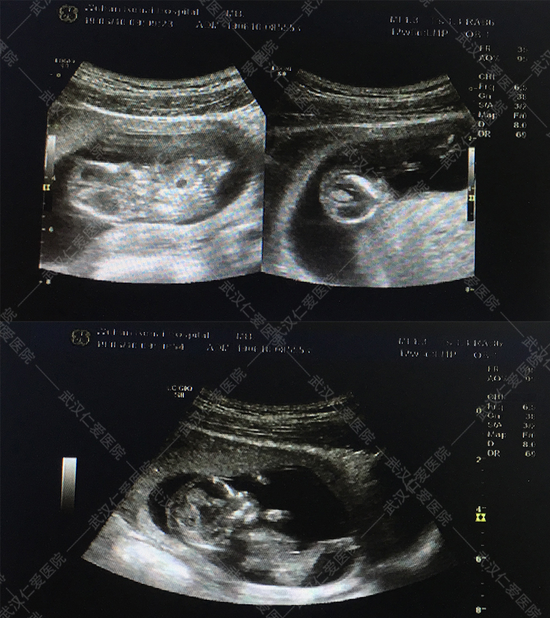

6月16號(hào),武漢仁愛(ài)醫(yī)院NT篩查出兩例畸形胎兒,一例多器官多系統(tǒng)畸形,一例露腦畸形,這兩位孕媽都是孕12周+,其中一位還是高齡產(chǎn)婦今年33歲,喜懷二胎,本來(lái)是高高興興的來(lái)做產(chǎn)檢,沒(méi)想到NT篩查出胎兒露腦畸形。

露腦畸形